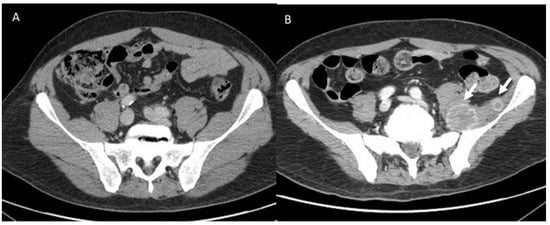

- Tirumani, S.H.; Ramaiya, N.H.; Keraliya, A.; Bailey, N.D.; Ott, P.A.; Hodi, F.S.; Nishino, M. Radiographic profiling of immune-related adverse events in advanced melanoma patients treated with ipilimumab. Cancer Immunol. Res. 2015, 3, 1185–1192. [Google Scholar] [CrossRef]

- Kwak, J.J.; Tirumani, S.H.; Van den Abbeele, A.D.; Koo, P.J.; Jacene, H.A. Cancer immunotherapy: Imaging assessment of novel treatment response patterns and immune-related adverse events. Radiographics 2015, 35, 424–437. [Google Scholar] [CrossRef]